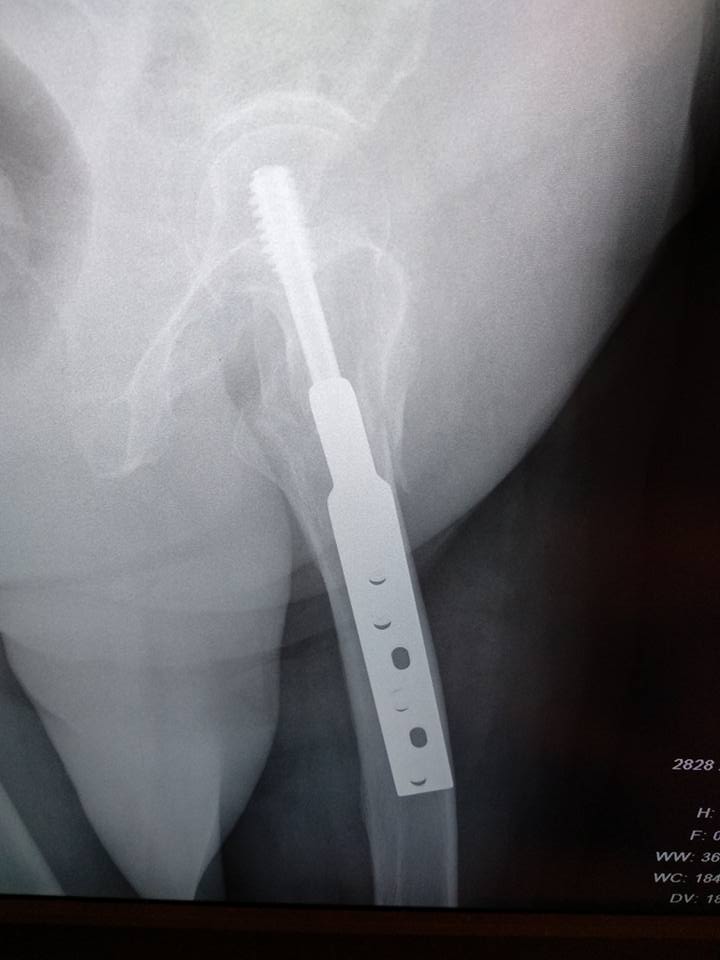

[Ortho] Межвертельный перелом после фиксации DHS

У пациентки операция неделю назад, к нам поступила с короткой выпиской и

без снимков. На контрольных рентгенограммах вот такая картина.

Непонятно, это вторичное смещение или так и было.. утверждает что не

наступала. 80 лет, сохранная, активная женщина. Нога болит, прилипшая

пятка, ротации, укорочения нет. Коллеги, какие мнения?